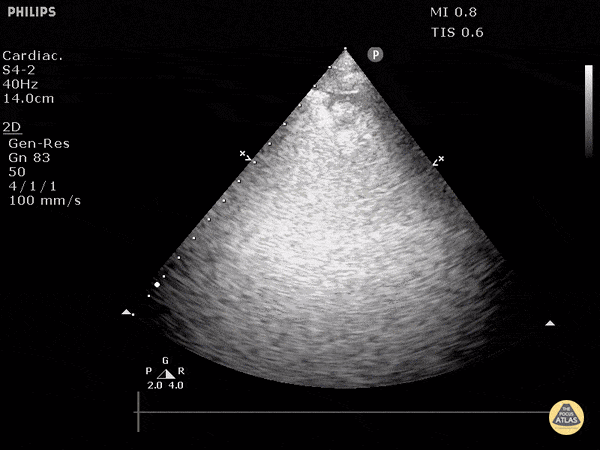

Pulmonary - Pulmonary Embolism (Sector Probe)

Pulmonary embolism can be seen by disruption of the pleural line. 0.5cm to 3cm disruptions are typical for PE. Doing DVT studies and echo can help strengthen your diagnosis. Dr. Justin Bowra et al.